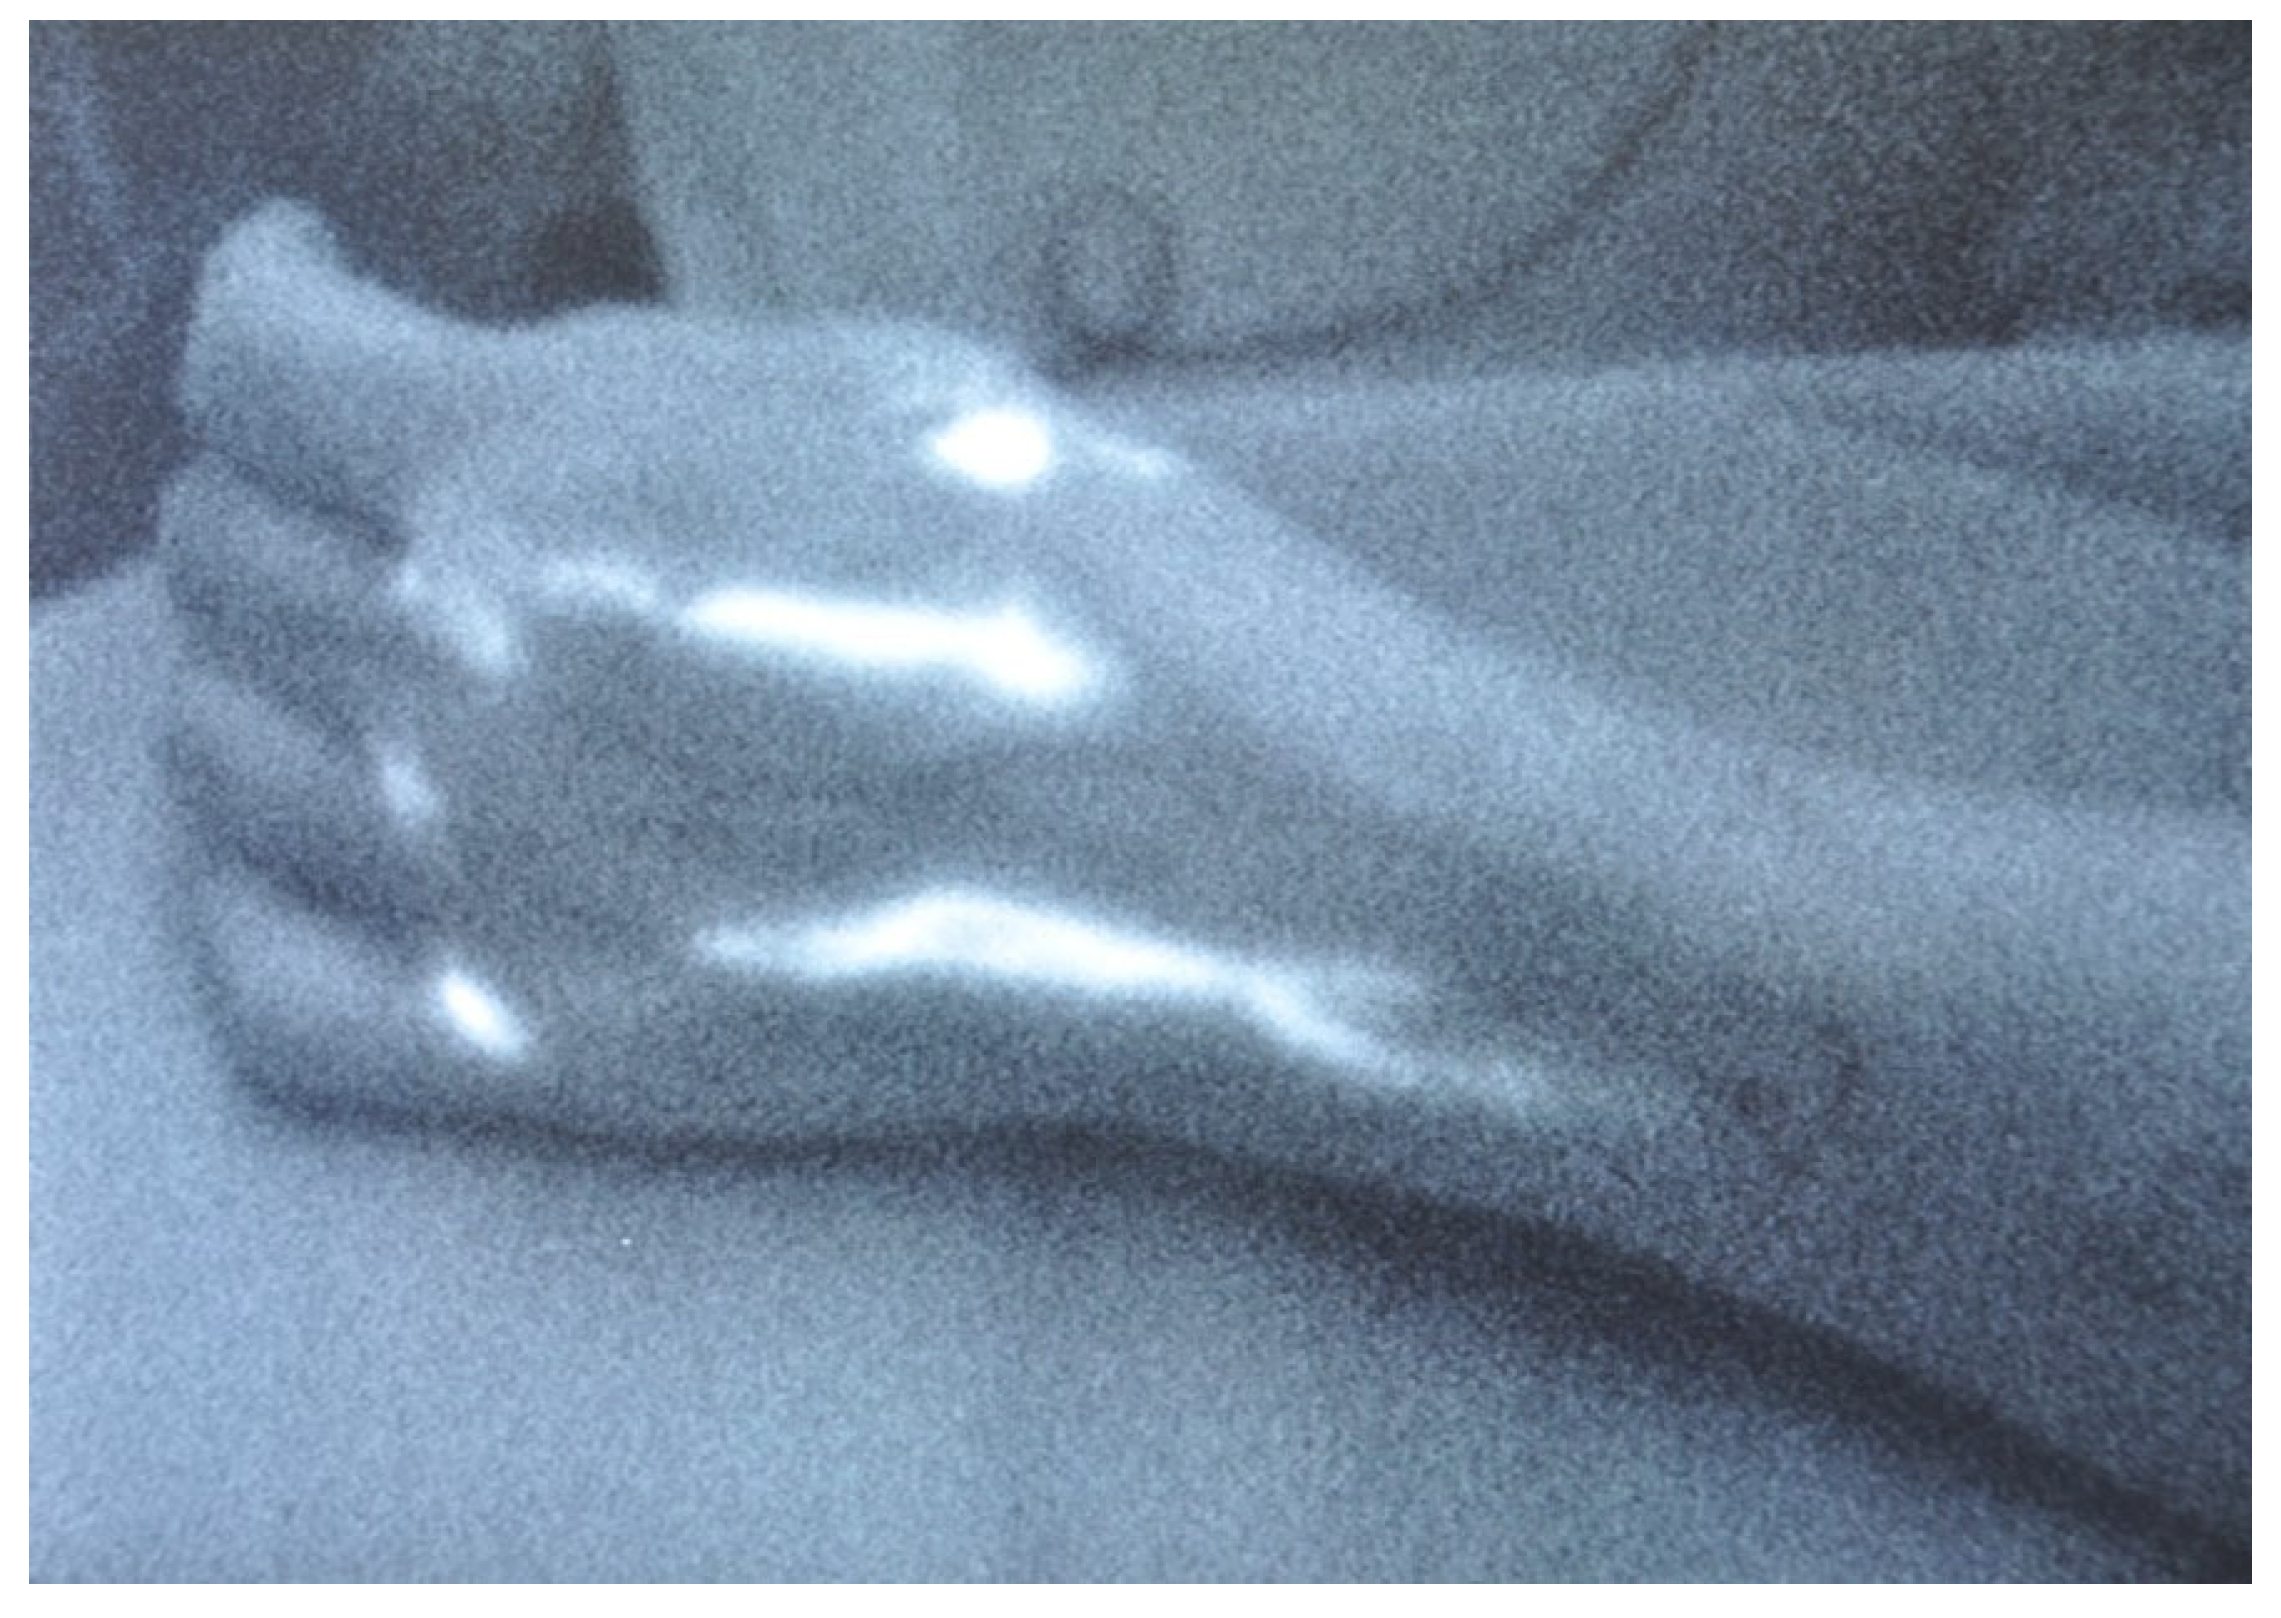

Figure 2.

Linear pattern demonstrated by ICG lymphography.

Indocyanine green lymphography (ICG-L) is currently the preferred diagnostic imaging technique for the lymphatic system among surgeons [8]. It has higher sensitivity and specificity for diagnosing lymphedema compared to lymphoscintigraphy [7]. It is also used for the selection of the surgical treatment modality and to give guidance to conservative treatment via manual lymphatic drainage. An intradermal injection of an ICG tracer in the distal limb is followed by the visualization of the lymphatic vessels under a near-infrared camera. It is a minimally invasive, simple, and highly accurate method for assessing lymphatic system status [9]. It enables the evaluation of the functional status of the superficial lymphatic vessels and the determination of their location, collateral lymphatic circulation, and dermal backflow [2,9,10]. A staging system correlating the disease severity with the pattern of dermal backflow on ICG-L was developed by Yamamoto et al. [11]. A linear pattern is considered to be normal, while splash, stardust, and diffuse patterns represent abnormalities with increasing levels of deterioration in lymphatic function (Figure 2). In severe cases of dermal backflow, the lymphatic flow beneath it is masked and cannot be detected by ICG-L. Other limitations include an inability to visualize lymphatic vessels deeper than 1.5–2.0 cm from the skin’s surface and an inability to assess interstitial tissues, the venous system, or the lymph nodes (except during surgery) [1,7,8,10]. Furthermore, the evaluation method is operator-dependent.